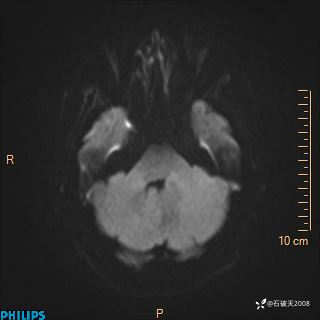

DWI